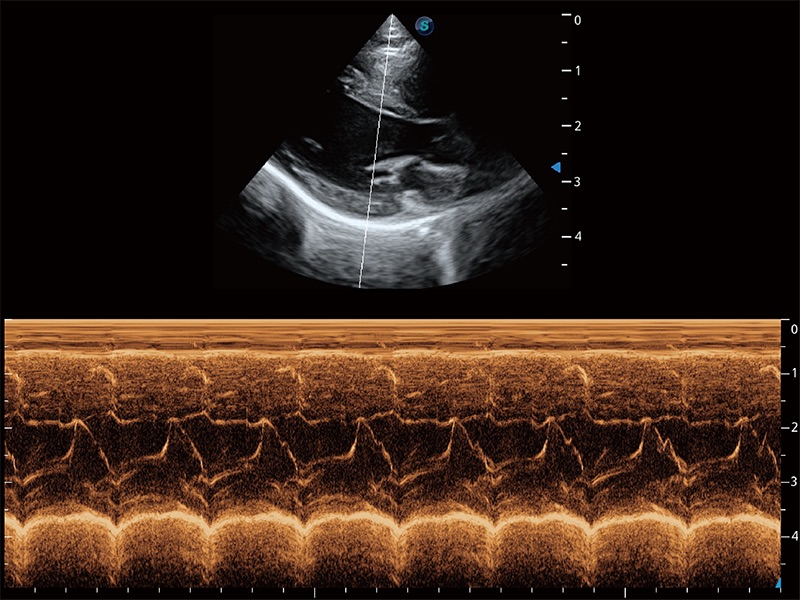

通过360度任意调节3条M型取样线,在同一心动周期上观察心脏不同位置的运动曲线,得到准确的心功能测量数据,有效评估心肌运动及左心室功能。

ProPet 80 配备了丰富的心脏探头群、先进的成像技术和专业的心脏测量工具,可帮助动物医生为不同体型和生理结构的动物提供心脏和心肌功能的全面评估。